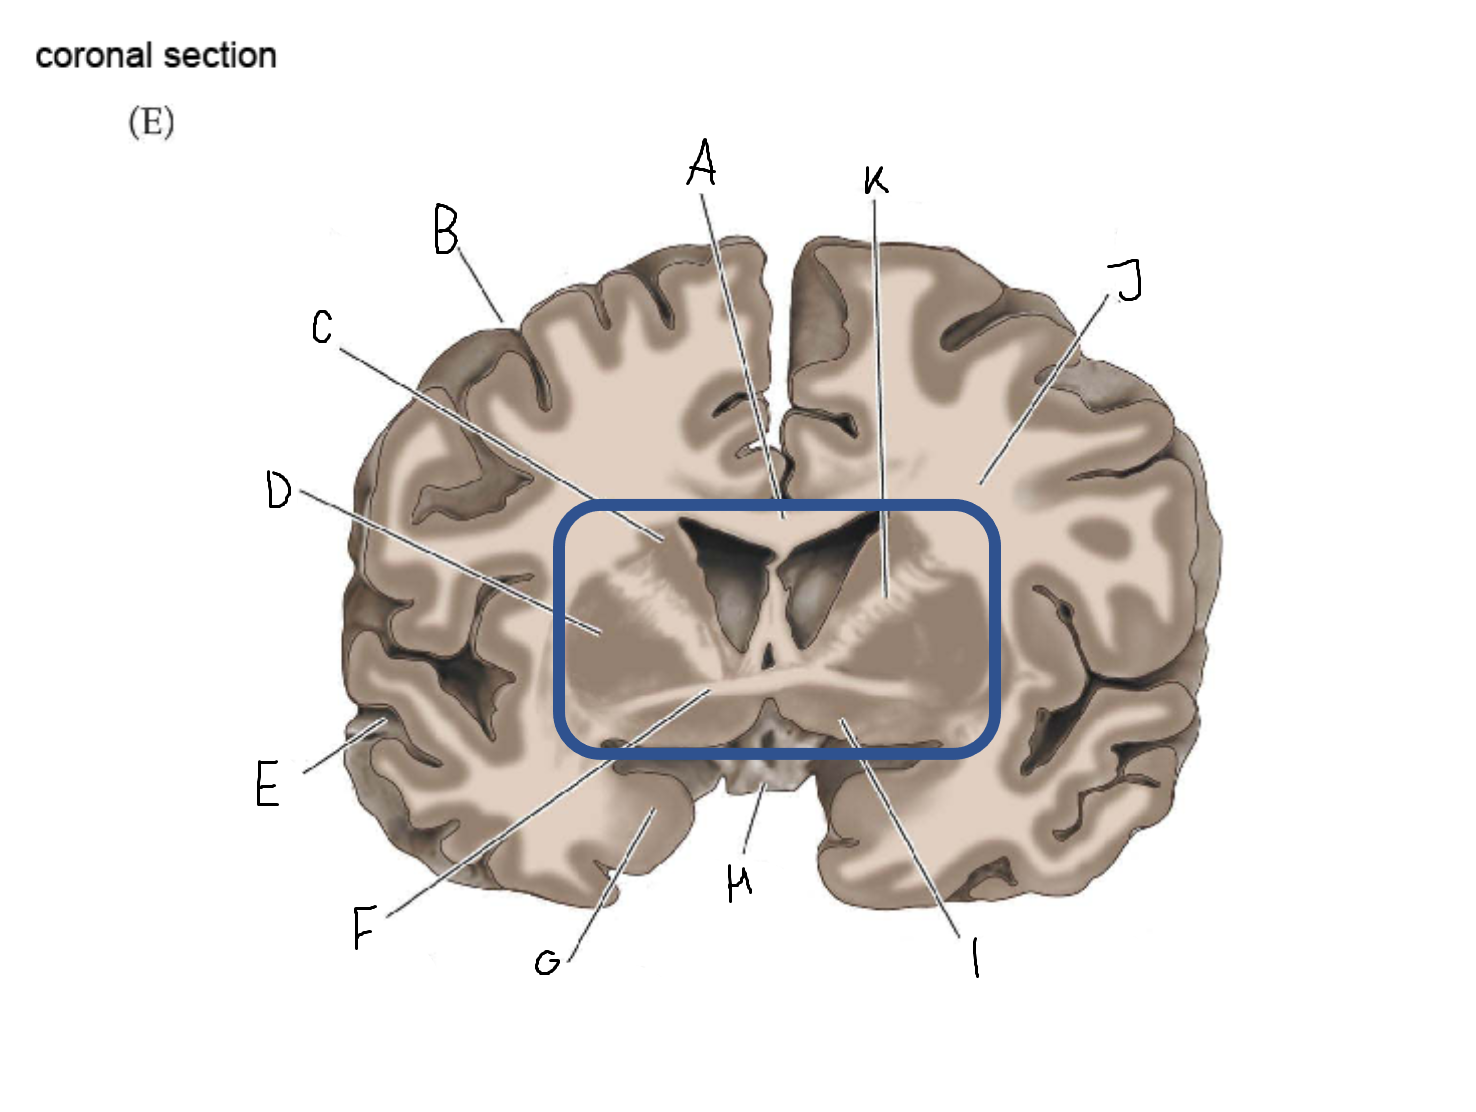

A

corpus callosum

B

cerebral cortex

C

caudate

D

putamen

F

anterior commissure

G

amygdala

H

optic chiasm

I

basal forebrain nuclei

K

internal capsule